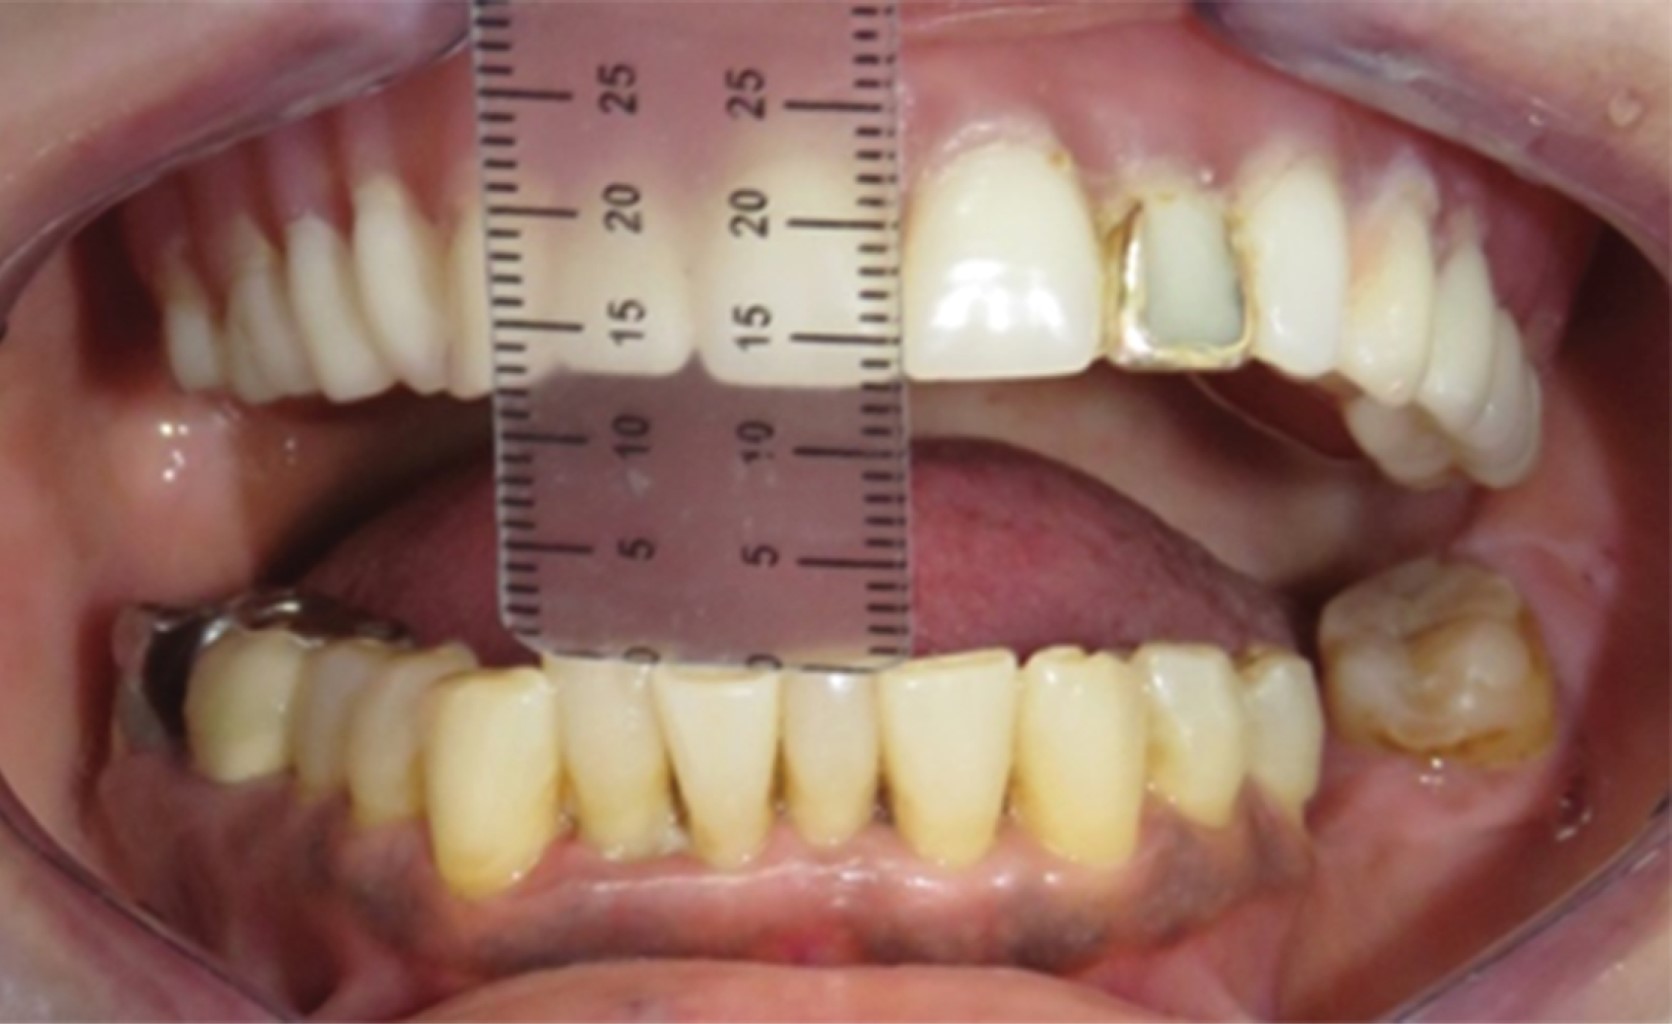

Se trató de una mujer de 60 años, la cual inició su padecimiento en octubre del 2014. Refiere antecedentes de una artroplastia de ATM izquierda en el 2005 y de la ATM derecha en el en el 2012. La paciente refirió dolor intenso de tipo punzante en la zona preauricular derecha durante la masticación, así como desviación mandibular a la apertura mínima, imposibilidad de adecuada alimentación y una limitación a la apertura de 13 mm (Figura 1). En la ortopantomografía (Figura 2A), tomografía y resonancia magnética se observa una anquilosis de ATM derecha tipo II, donde se identifica el cóndilo mandibular deformado con una fusión en el borde externo de la cavidad glenoidea (Figura 2 B y C). La ATM izquierda presenta el cóndilo deformado, pero sin presencia de adherencias de importancia. En un modelo estereolitográfico se diseñó la osteotomía, artroplastia y remodelación, así como la adaptación del acetábulo y prótesis condílea de stock o prefabricada (Biomet Microfixation)30 (Figura 3 A y B).

CASO 2

Figura 1